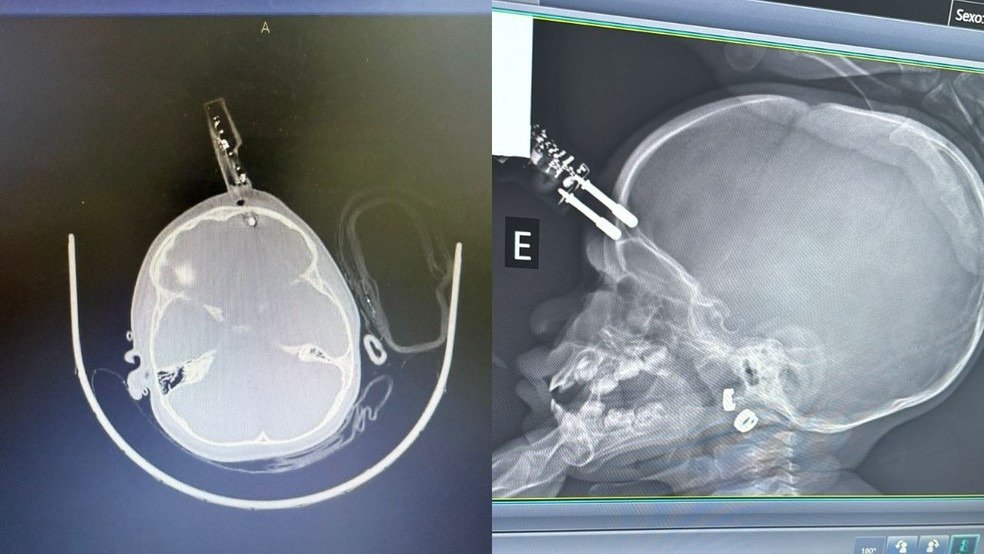

Uma menina de 1 ano passou por uma cirurgia de urgência após cair da cama e ter um carregador de celular cravado na testa, em Divinópolis. Ela segue internada, em observação, sem sinais de sequelas neurológicas até o momento, segundo o médico responsável pelo atendimento, o neurocirurgião Bruno Castro.

O médico disse que teve a informação de que a mãe da criança havia ido ao banheiro no momento do acidente, na última terça-feira (13). A principal hipótese é que a menina estava com o carregador na mão quando caiu da cama e o objeto atingiu a cabeça de forma que perfurou a região frontal do crânio, perto do olho.

“A única possibilidade que eu acredito é que ela estava com o carregador na mão e caiu junto com ele da cama e, por azar, ele bateu de um jeito que entrou na cabeça dela. Se tivesse atingido o olho, poderia ter causado perda da visão. Felizmente, isso não aconteceu”, explicou Castro.

A criança foi levada imediatamente ao bloco cirúrgico, onde passou por procedimentos de limpeza, retirada do objeto, lavagem, fechamento e reconstrução da área atingida.

Castro explicou que o principal risco em situações como essa é a lesão cerebral. Segundo ele, o objeto perfurante atravessou o osso do crânio e atingiu o tecido cerebral, o que poderia provocar hemorragia.

“O maior risco do ponto de vista neurológico é o trauma e a lesão cerebral. Esse objeto atravessou o crânio, fincou no cérebro e isso pode ocasionar hemorragia”, afirmou.